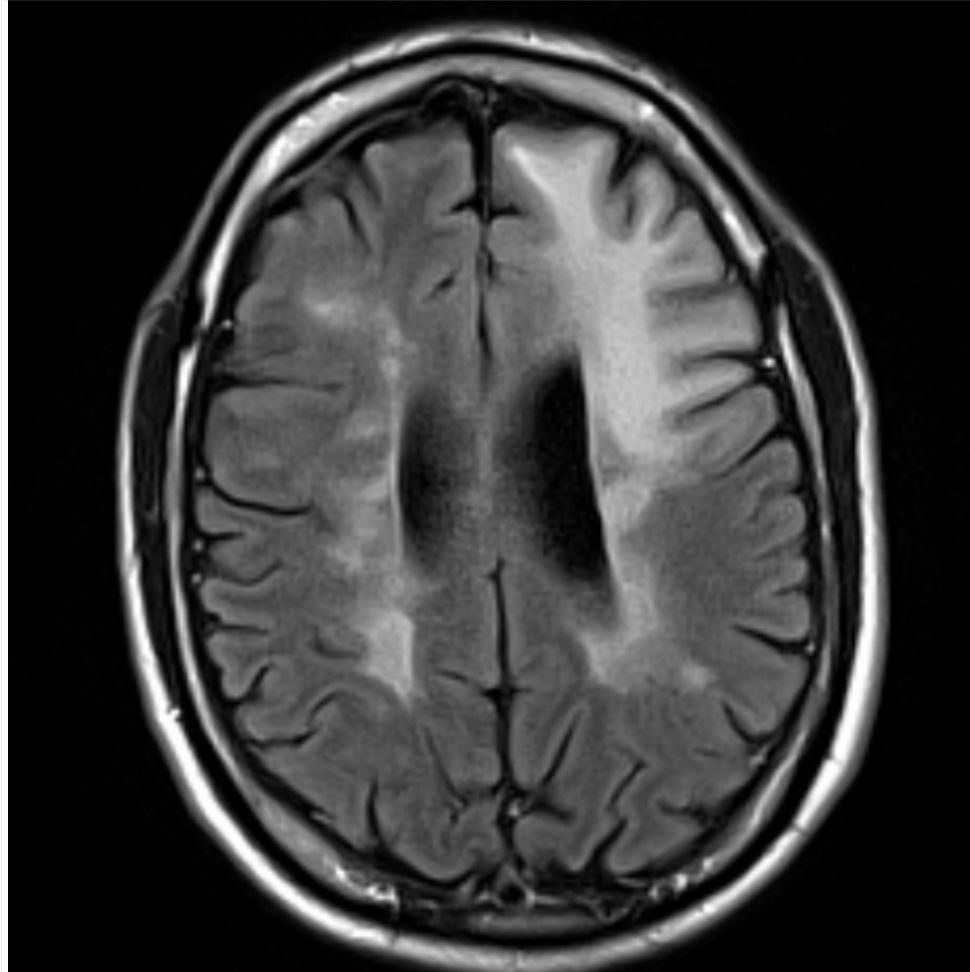

A 30 year-old female presented with with double vision.

Multiple sclerosis - lesions in corpus callosum